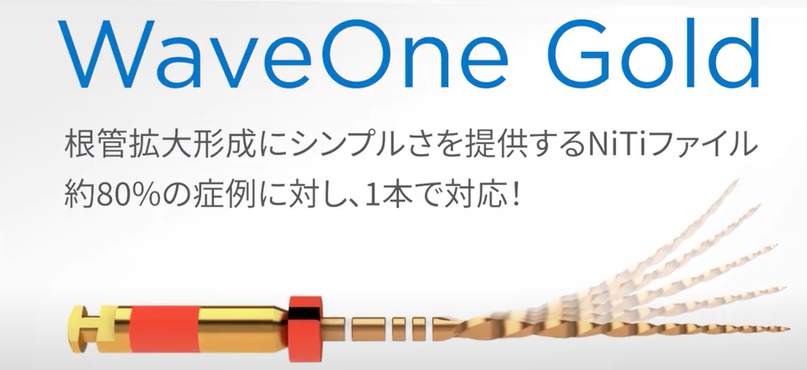

ニッケルチタンロータリーファイル

ニッケルチタンという金属で出来た、根管治療用の器具です。

このように強く曲がった歯の根管治療は、従来のステンレススチール製の器具では、思うように根の先端まで治療できなかったのですが、超弾性という性質を持つニッケルチタン製の器具であれば、このような強く曲がった根管でも、治療が可能となりました。

そして、ロータリーファイル、というのは機械につけて使う物なのですが、手で行っていた従来の方法と比べて、治療がはやく進み、口を開けている時間や通院日数の短縮も可能となりました。